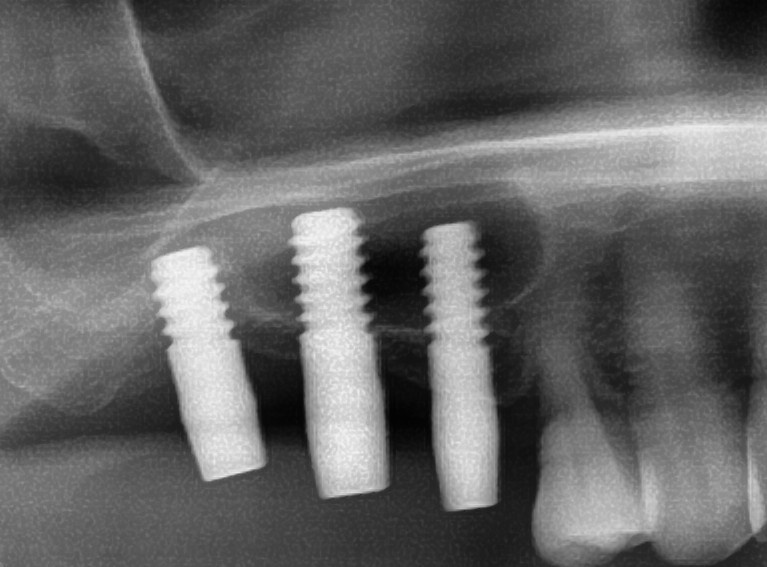

続けて他の歯も同じように植立していきます。

インプラントオペでは、複数本を植立する場合でも、当時進行はせず、1本ずつ同じ工程を繰り返して植立します。

しっかりとインプラント埋め込まれた後は、動揺がないか、噛んだ時に当たらないかなどを確認して、最後にパノラマ写真を撮影して今回のオペは終了となりました。